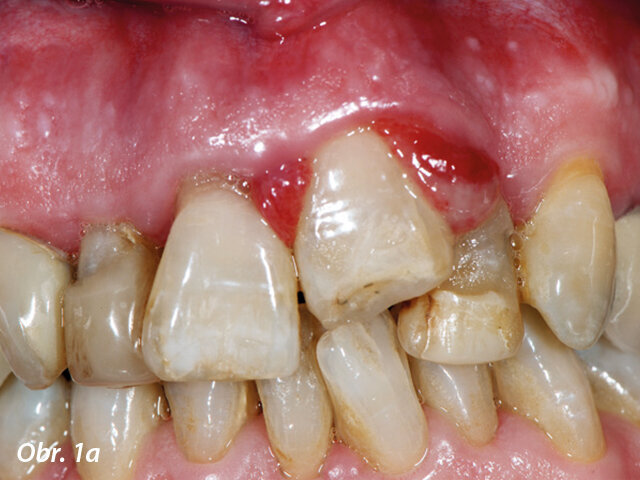

Traumatická intruze, laser byl použit před ortodontickou extruzí kvůli možným bolestem.